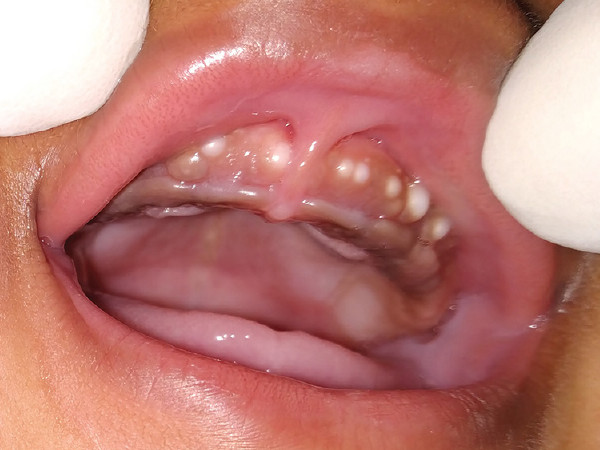

BOHN'S NODULES home ICD10: K09.8

Bohn’s nodules zijn kleine cysteuze afwijkingen op de gingiva van pasgeborenen. Het komt vaak voor, bij tot circa 85% van de neonaten kunnen ze worden aangetroffen. De oorzaak is niet bekend. Mogelijk gaat het uit van resten van dentogeen epitheel of epitheel van speekselklieren. Het is een onschuldige aandoening, die vanzelf weer over gaat.

Bohn’s nodules

Foto: Kaul R et al. Journal of Oral Research and Review 2022;14:42 (Creative Commons License 4.0 - Public Access Journal).